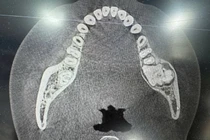

Chẩn đoán hình ảnh: Hầu hết các nang được phát hiện tình cờ qua X-quang định kỳ. Nang xuất hiện dưới dạng vùng thấu quang với viền rõ; CT cone-beam, MSCT: Cung cấp hình ảnh 3D chi tiết về kích thước và vị trí nang.

Nang xương hàm - Ảnh BSCC